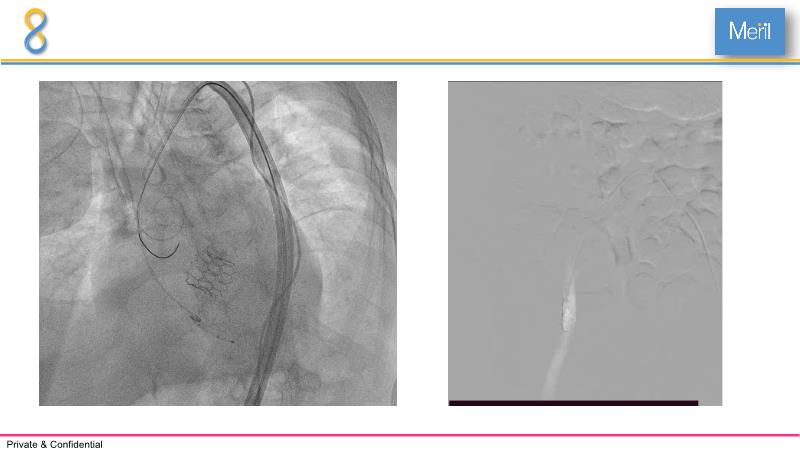

Through the presentation of several compelling cases, including an 88-year-old male with CKD, RBBB, moderate LV dysfunction, and severe aortic stenosis, a Type 1a bicuspid native AS, and an extraordinary TAVI in an 83-year-old with acute heart failure and comorbidities, this session will dive into the Myval Octapro THV. Learn about its key features, procedural impact, and potential clinical benefits. Discover the Octalign technique for predictable and precise commissural and coronary alignment, preserving coronary access. Gain insights into precise sizing, positioning, and deployment of the Myval THV series in real-world scenarios, and explore the relevance of pivotal Landmark RCTs in clinical practice.

- To learn about the novel Myval Octapro THV - Key features, the procedural impact and potential clinical benefits.

- To understand the technique of precise sizing, positioning and deployment of Myval THV series in real world clinical scenarios